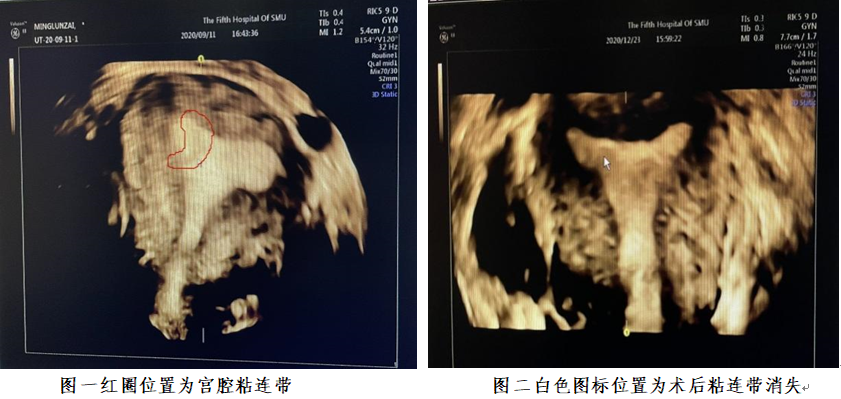

心灰意冷的她半信半疑,多方打听,最后得知南医五院超声医学科邱建民主任是超声诊断方面的权威专家、岭南名医,擅长各种疑难病例的超声诊断,具有丰富的经验。于是她慕名找到了邱建民主任做四维子宫彩超检查。检查中,邱主任详细询问患者情况,一边认真细致地帮她检查,一边凭借着丰富的经验,“火眼金睛”对仪器显示屏数据信息进行分析判断。最后检查发现:患者宫腔形态正常,自右侧中上段向宫底延伸不规则带状低回声,范围约28×17mm,考虑为宫腔粘连带。

不是子宫纵膈,是宫腔粘连!闵女士当时就很震惊,做了那么多次B超和输卵管造影竟然都没有发现这个问题。据了解,宫腔粘连被称为女性备孕路上的“拦路虎”,不同于先天性疾病的子宫纵隔,宫腔粘连是因宫腔炎症等因素导致的局部或完全宫腔粘合在一起,更容易导致不孕或孕早期流产。不管是常规B超或者四维彩超检查都难以诊断发现,需要丰富的临床经验和技术。闵女士这才醒悟原来自己在求医的道路上走了不少弯路!

随后,闵女士进行了宫腔镜下的宫腔粘连分离手术以及药物治疗。三个月后,闵女士再次找到了邱主任进行复查,检查结果显示宫腔内未见明显异常。复查后的一个月,闵女士发信息告诉邱主任,自己自然怀孕了,于是就出现了本文开头的一幕。细心的邱主任还不忘叮嘱闵女士,要注重后期的产检。